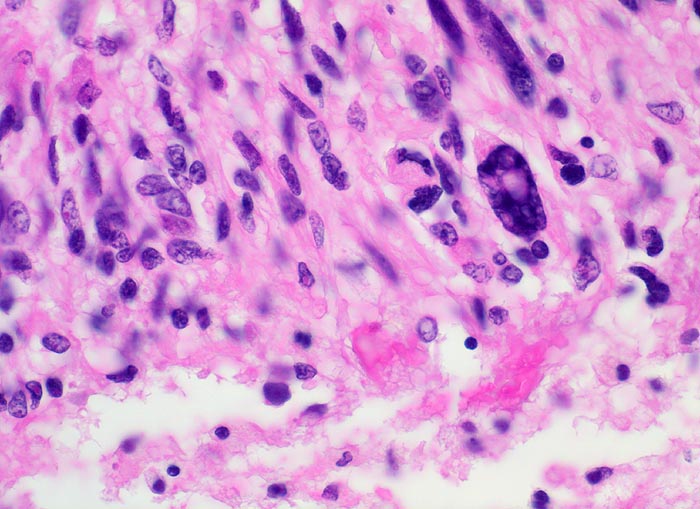

PathoPic ID 5203 - Glioblastoma multiforme (WHO IV)

Glioblastoma multiforme (WHO IV)

maligner Tumor

Hirn temporal

Nervensystem

Hohe Zelldichte, ausgeprägte Kern- und Zellpolymorphie mit hyperchromatischen unregelmässig geformten Zellen.

Seit zwei Monaten zunehmende Persönlichkeitsveränderungen, Kopfschmerzen und progrediente fokal neurologische Zeichen.

Histologie

400